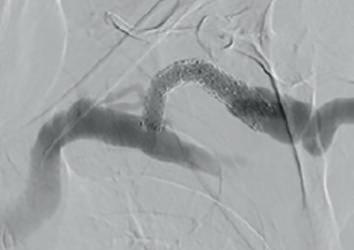

Example procedural outcome: treatment of Bond’s patient with a left brachiocephalic AVF that presented with a stenosis at the cephalic arch with aneurysmal segment.

(A) Fistulogram taken preintervention and (B) after deployment of WRAPSODY to treat. (C) Fluoroscopy of treated segment at 18 months (D) and patient’s arm at time of presentation

Bond was the first in the world to commercially implant Wrapsody CIE three years ago. “The first patient I remember well,” he says. “She had a left brachiocephalic fistula that had been put in place in 2014, and it had been working in the two years before I saw her in 2019. The main problem was that she was getting a lot of pain when the AVF was used for haemodialysis, and it was taking five to six hours to dialyse.” He adds that she “experienced bleeding from the fistula following dialysis.”

Bond explains that she was diagnosed with a particularly tight cephalic arch stenosis. Despite four previous treatment attempts by the radiology team rapid restenosis of her cephalic arch occurred each time. With her referral to Bond and the renal team, the initial treatment plan was to ligate the fistula. However, Bond opted for the Wrapsody CIE instead.